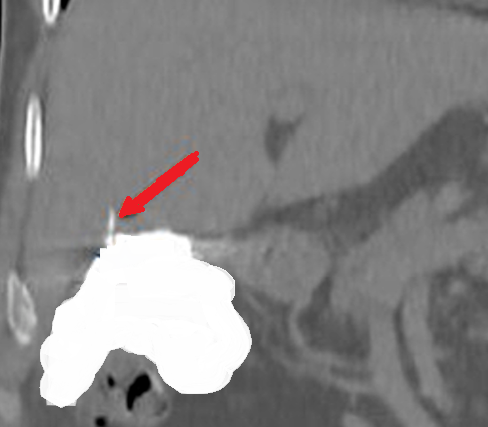

Patient CT, 6th postoperative day. Contrast in the gallbladder fossa. Red arrow — Injured Luschka duct (Courtesy Dr. V. Penopoulos)